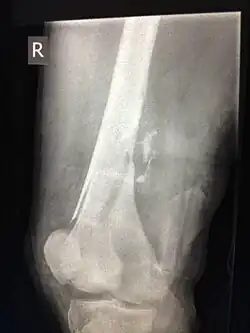

Sind beim Einschuss Knochen betroffen, so tritt meist eine ausgedehnte Zersplitterung (Schussfraktur) ein.